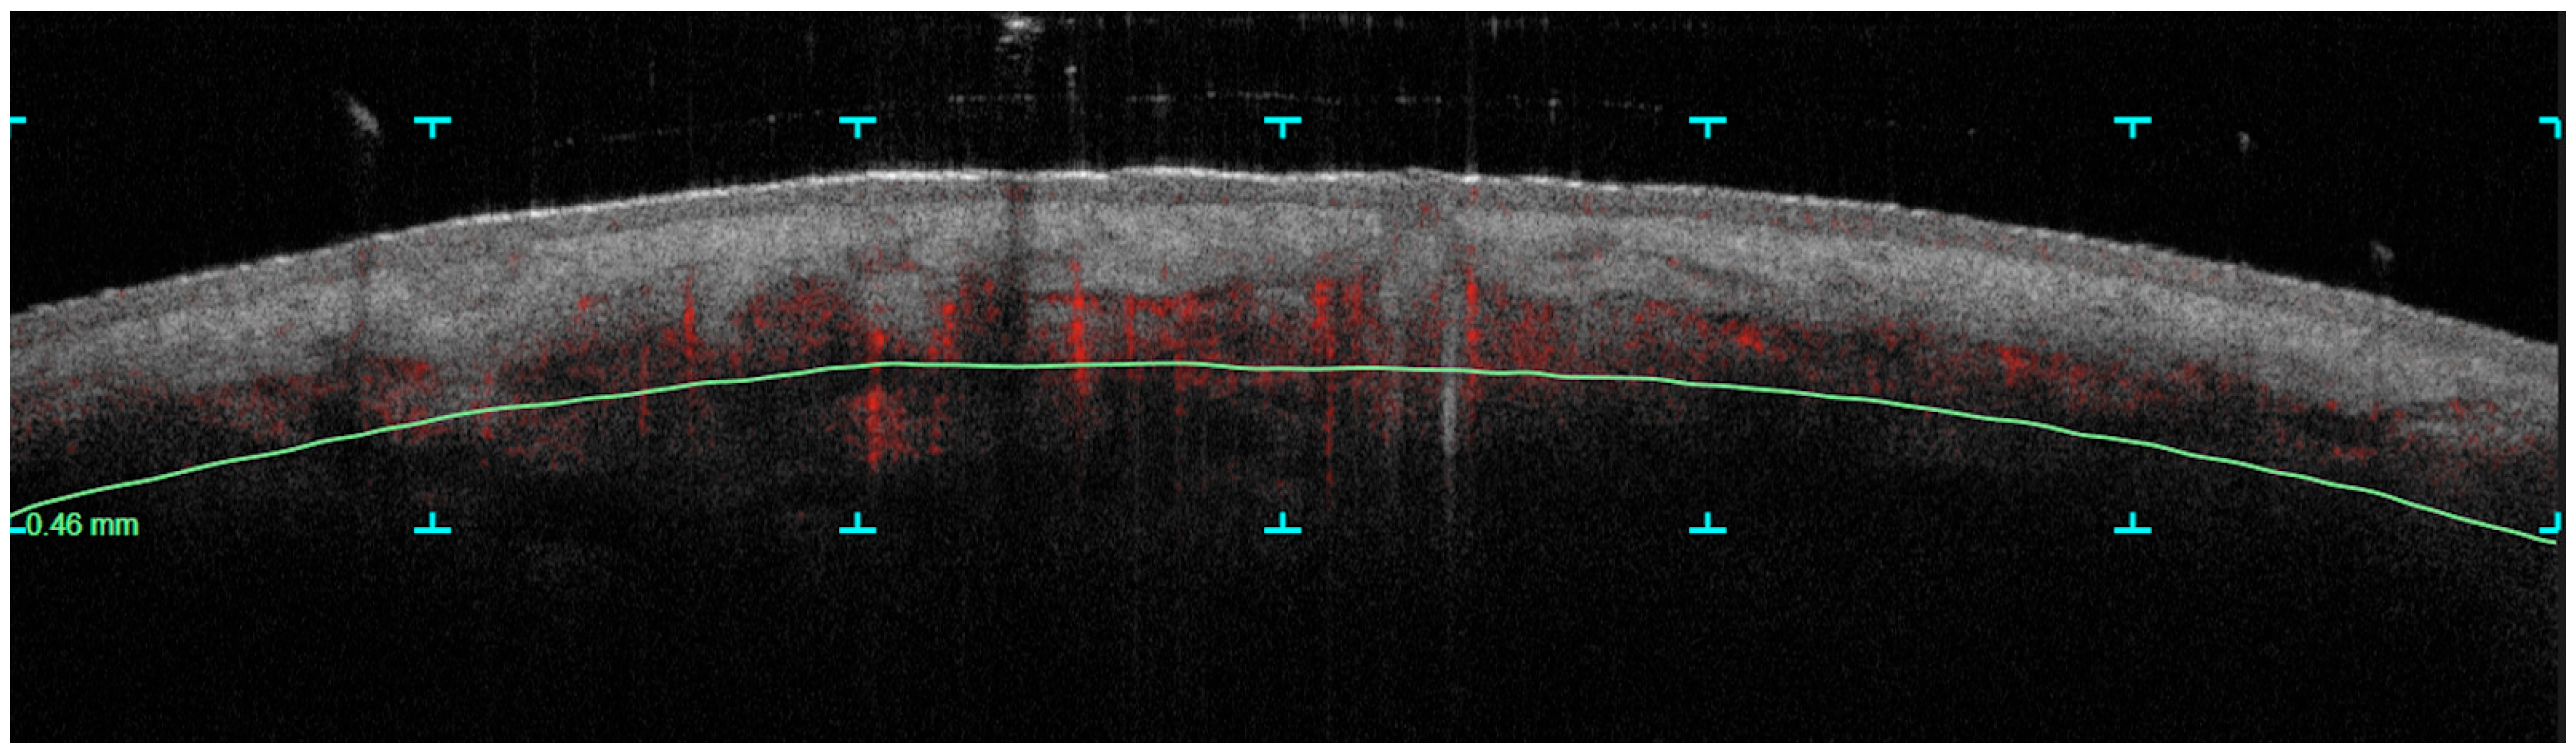

Dynamic OCT Data Analysis

- Vascular density

- Collagen density

3.1. Vascular Density Changes

- The Vascular Density at 300 µm and 500 µm shows a notable decrease in mean values from pre-treatment to post-treatment, with the p-values (1.03 × 10–141.03 × 10−14 and 1.35 × 10–151.35 × 10−15, respectively) indicating this reduction is statistically significant.